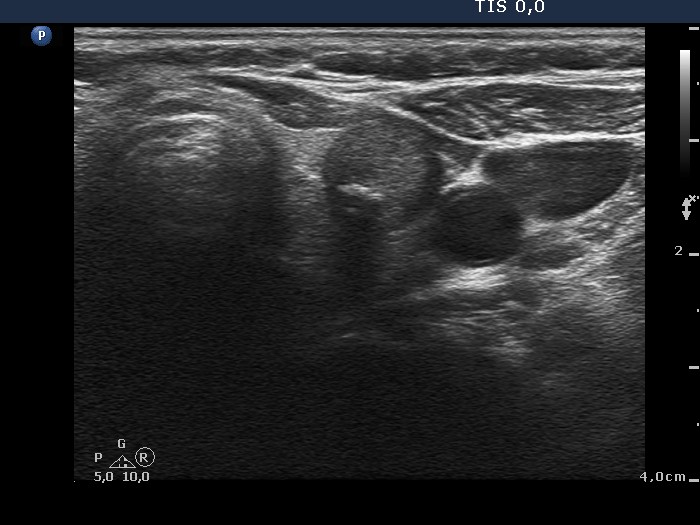

Ultrasonography. The thyroid was echonormal. Beside small hypoechogenic discrete areas there was one hypoechogenic nodule in the right, while two moderately hypoechogenic lesions in the left lobe. The nodule in the upper third of the left lobe was suspicious on ultrasound because of the presence of microcalcifications.

Histopathology disclosed three different entities corresponding to the three nodules found on ultrasound: the right lesion proved to be a hyperplastic nodule, the upper left nodule a classic variant of papillary carcinoma while the lower left lesion did a microfollicular adenoma. Another focus of papillary carcinoma was found in the right lobe with a maximal diameter of 1.5 mm, which was a dominantly follicular variant of papillary carcinoma.

The nodule in the lower pole of the left lobe has lobulated/spiculated margins.

Both the malignant nodule and the oxyphilic adenoma present all three possible signs which might suggest extrathyroidal extension: abutment, bulging and discontinuation of the thyroid capsule. The malignant tumor spread into the capsule but did not break it.